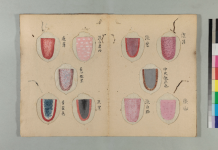

舌質正常・苔薄白・脈弦。

舌質淡・舌苔少・脈沈弱。

舌淡・脈弱無力。